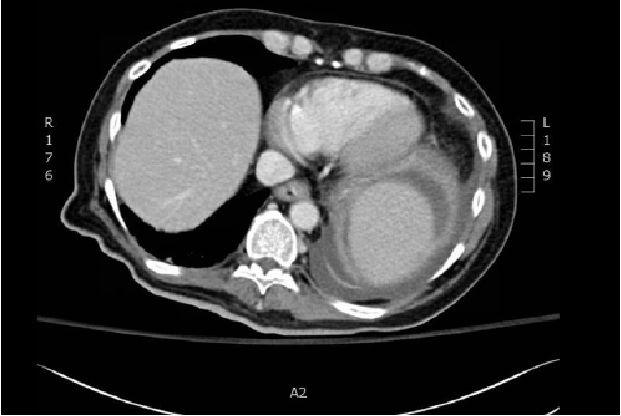

背景介绍:一个89岁的日本男子吐血带来我们医院。增强CT显示胃和胰腺之间的11×10×10厘米*小单大**房性囊性肿瘤(图A,箭头)。胃镜检查:发现一个大在胃体上部大弯的软凸起,凸起表明面有一个易碎的溃疡(图B)。病人入院后12天接受胃部分切除术。组织学上,被切除的标本被发现是囊性病变并有部分钙化(图片C)。囊肿包括浆液和血液,病理分析为梭形细胞成分,且c-kit和CD34免疫组化阳性(图片D)。有丝分裂率为10/50个高倍视野,根据弗莱彻的危险分级诊断为胃肠道间质瘤(1)。大多数胃肠道间质瘤为实性肿瘤,囊性改变少见(2)。这种情况下囊性改变可能是由于肿瘤的快速生长和坏死引起的。这种情况下囊性改变可能是由肿瘤的快速生长和坏死引起的。胃肠道间质瘤表现为单房性囊性病变,虽然罕见,应于上腹部囊性病变的鉴别诊断。